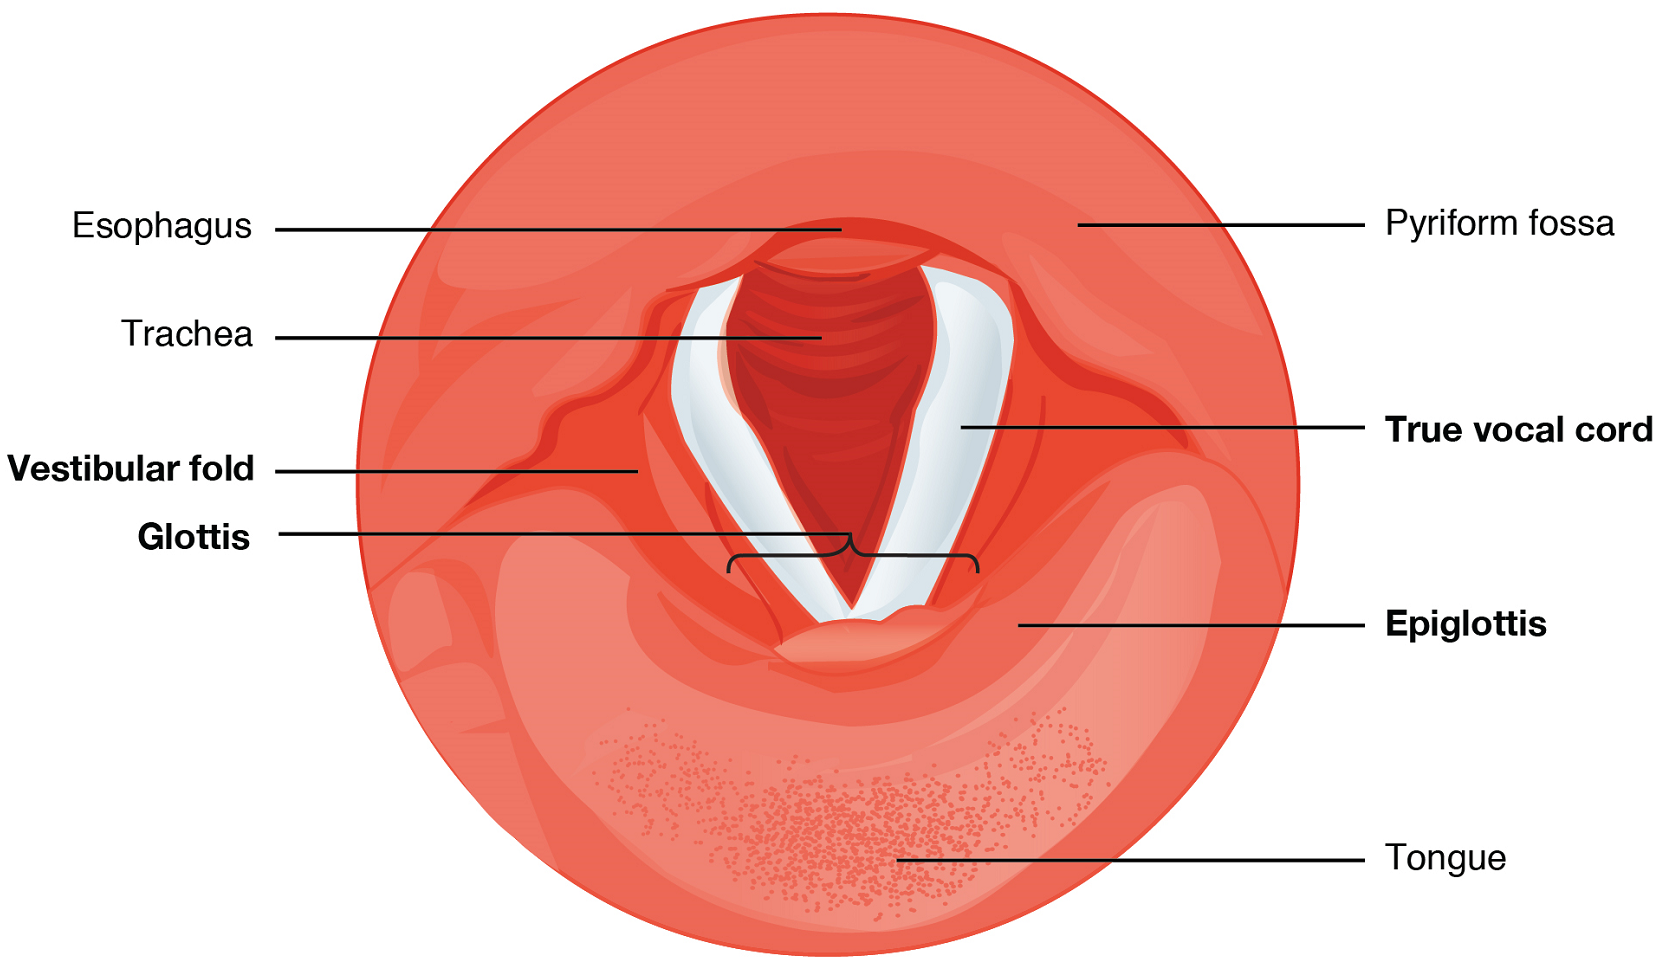

Larynx: The larynx is a cartilaginous structure inferior to the laryngopharynx that connects the pharynx to the trachea and helps regulate the volume of air that enters and leaves the lungs. The structure of the larynx is formed by several pieces of cartilage (Figure 4). Three large cartilage pieces—the thyroid cartilage (anterior; which contains the Adam’s apple or laryngeal prominence), epiglottis (superior), and cricoid cartilage (inferior)—form the major structure of the larynx. Other smaller, paired pieces of cartilage help move the vocal cords for speech.

The epiglottis is a very flexible piece of elastic cartilage that covers the opening of the trachea (see Figure 2). When in the “closed” position, during swallowing, the unattached end of the epiglottis rests on the glottis preventing food and beverages from entering the trachea (as will be described in the digestive system section). The glottis is composed of the vestibular folds, the true vocal cords, and the space between these folds (Figure 5).